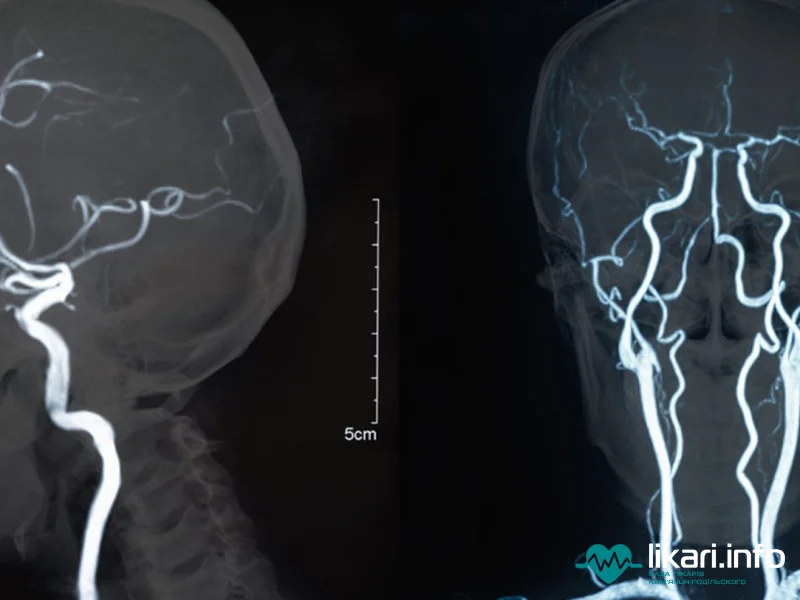

Магнітно-резонансна томографія (МРТ) судин головного мозку ґрунтується на впливі електромагнітних хвиль та є високоспеціалізованим різновидом МРТ, часто званим Магнітно-резонансною ангіографією (МРА).

Цей метод дозволяє отримати ряд детальних знімків у дво- або тривимірній площині для виявлення численних патологій судинної системи та мозкових тканин. До ключових особливостей методу належить відсутність шкідливого променевого впливу на організм людини, що робить його абсолютно безпечним. МРА дозволяє отримати максимально точні дані щодо стану кровотоку пацієнта.

Magnetic Resonance Imaging (MRI) of cerebral vessels is a highly specialized variant of MRI, often referred to as Magnetic Resonance Angiography (MRA). This technique utilizes electromagnetic waves to provide detailed two- or three-dimensional images crucial for detecting multiple vascular pathologies and brain tissue changes.

A key feature is the absence of harmful radiation exposure, making it a very safe procedure. MRA provides the most accurate data on the patient's circulatory health.